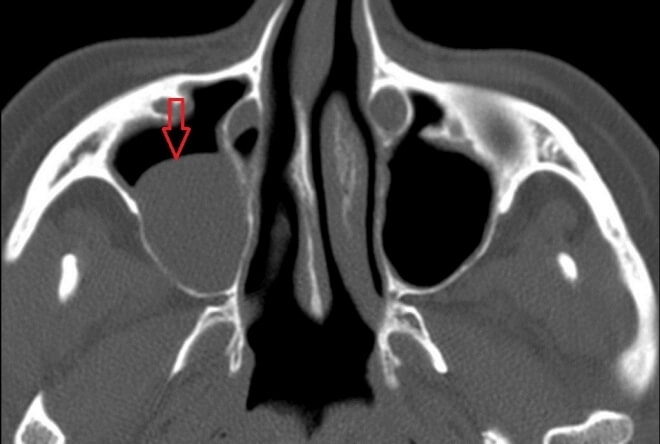

- Рентгенография придаточных синусов – кистозные образования на снимке выглядят как округлые тени; для точности рекомендуется делать снимки в двух проекциях.

- МРТ или КТ – если рентгенография недостаточна, назначается компьютерная томография. Магнитно-резонансная томография используется при признаках поражения мягких тканей.